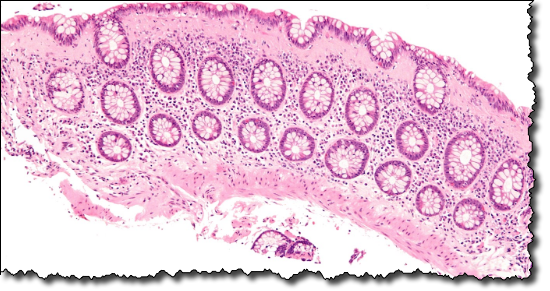

Here’s what a leaky gut looks like:

And here’s what a tight gut looks like: